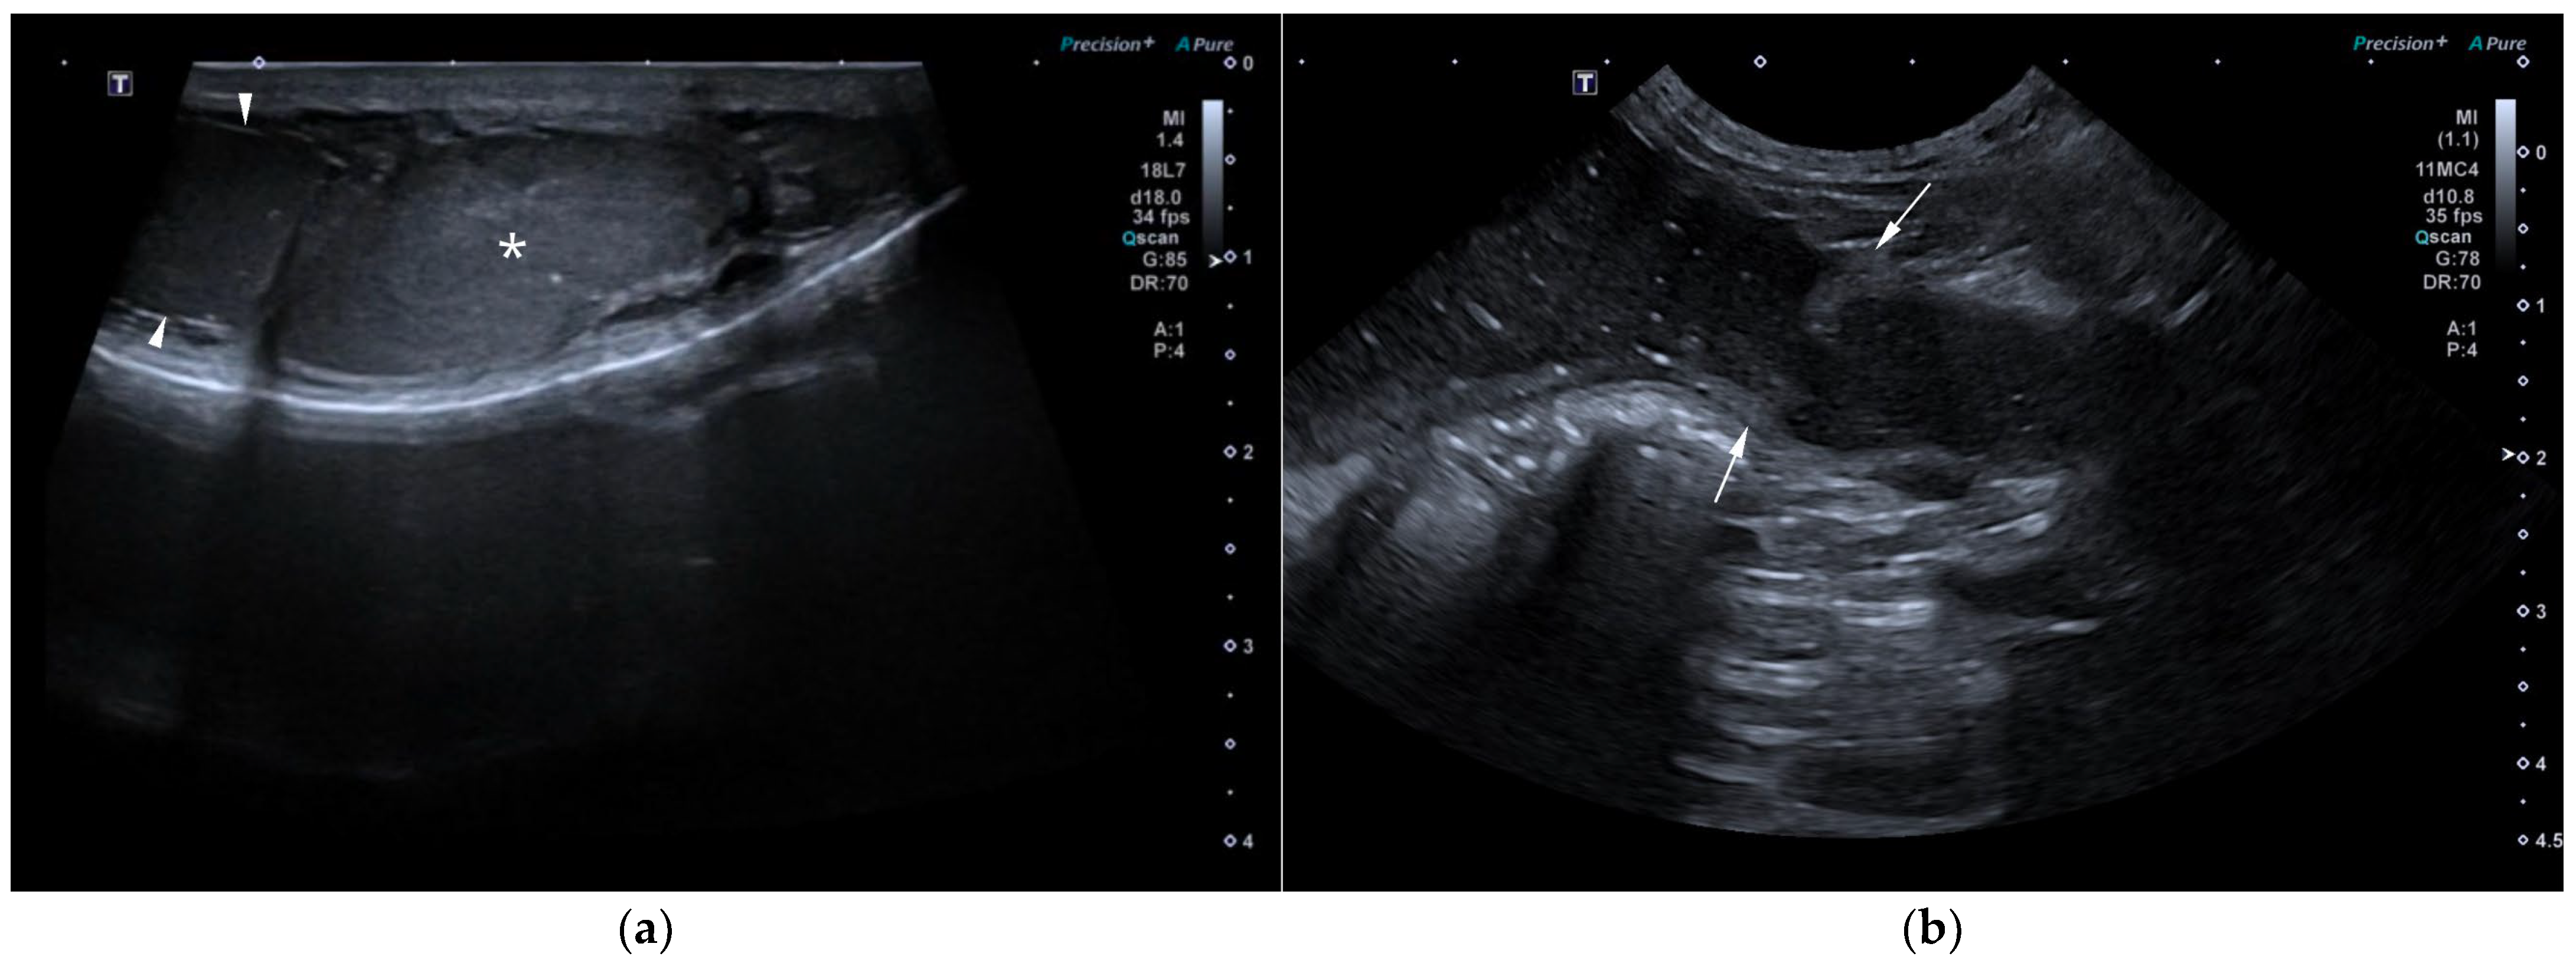

AUS in all three dogs revealed a fluid-filled cavitary structure originating in the caudal peritoneum between the colon and urinary bladder and extending cranially through the mid-abdomen, causing a mass effect. In cases 1 and 2, the lesion continued bilaterally as paired, thin tubular extensions coursing caudally through the inguinal rings adjacent to each testis (Figure 1a). In case 1, a focal mural narrowing resembling a uterine cervix was noted caudally (Figure 1b). The wall was thin and smooth in case 1, while in case 2 it was irregular, especially in its caudal aspect (Figure 2a,b). No information was available regarding the course of the UM horns or wall appearance for case 3. The luminal content consisted of echogenic, inhomogeneous fluid in all cases (Figure 3a); in case 2, sedimentation created fluid–fluid levels (Figure 3b).

Additional findings in all dogs included: enlarged, heterogeneous, cystic prostate; echogenic sediment in the urinary bladder; free peritoneal fluid [moderate and echogenic in case 2 (Figure 2a); mild and anechoic in cases 1 and 3]; and bilateral medial iliac lymphadenomegaly (moderate in cases 2 and 3; mild in case 1).

Figure 2. AUS of case 2: (a) Longitudinal view of the caudal UM, showing irregular wall margins (arrows), intraluminal inhomogeneous fluid, and free echogenic peritoneal fluid (arrowheads); (b) Detailed view of the UM wall demonstrating luminal irregular margins (arrows).

Figure 3. (a) AUS of case 1; transverse view of the most dilated UM segment containing inhomogeneous echogenic fluid; (b) AUS of case 2; oblique view showing two sections of the UM containing a moderate volume of sedimented material (asterisks), creating marked fluid–fluid levels.